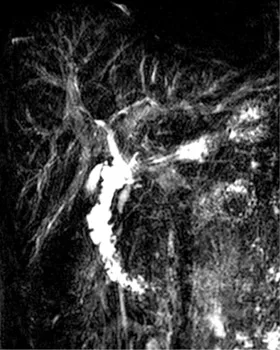

Figure 23. A. Chez ce patient greffé hépatique, la bili-IRM montre une sténose biliaire relativement longue (tête de flèche) en regard de la région anastomotique. Les voies biliaires d’amont ne sont pas dilatées.

B. Sur ce contrôle effectué dans un contexte de majoration de la cholestase, on constate l’apparition d’une collection liquidienne en regard de la région anastomotique (têtes de flèches), et une discrète augmentation du calibre des voies biliaires en amont.

C. Une acquisition tardive après injection d’un produit de contraste à élimination biliaire retrouve la présence de contraste dans la VB sus-anastomotique (flèche), ainsi que son passage dans la collection hilaire (têtes de flèches) : ceci confirmela fuite biliaire anastomotique